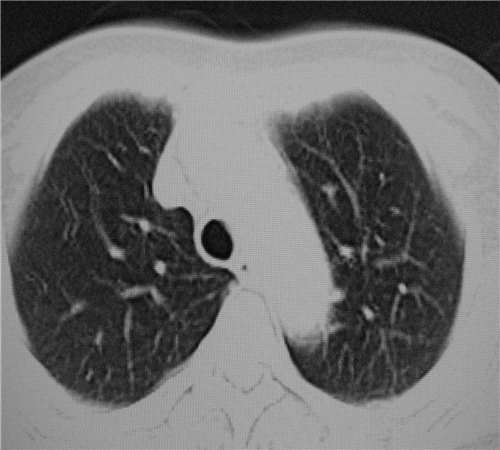

标题: CT26849:女67岁反复胸痛两天余,临床考虑夹层。 [打印本页]

标题: CT26849:女67岁反复胸痛两天余,临床考虑夹层。

右肺感染,未见夹层。

既然考虑夹层,建议强化!另:右下肺感染!

1)右肺感染性病变。2)建议行ct增强扫描或mri检查排除主动脉夹层。

双下肺感染,右侧显著。有无夹层,增强扫描后再诊断。

1. 感染性病变,2.未见夹层,3.食道未见异常。